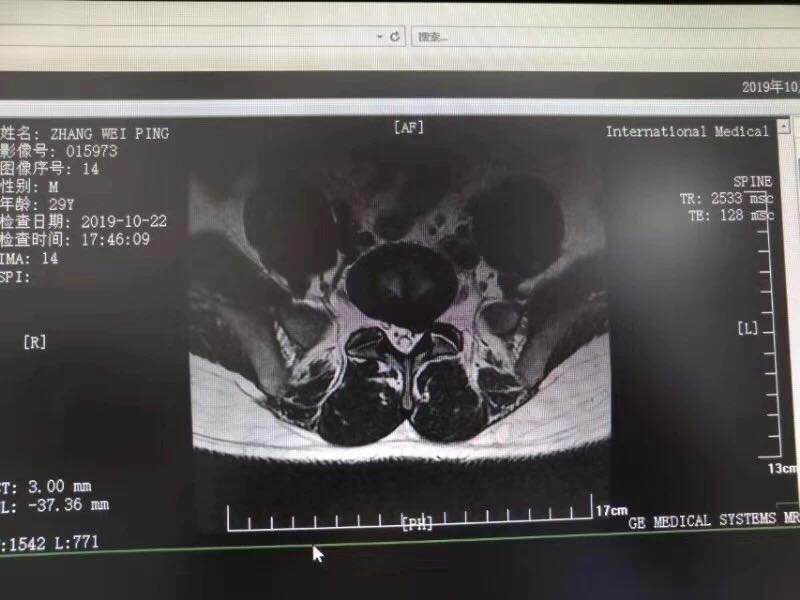

10月28日,西安國際醫(yī)學中心骨科醫(yī)院脊柱外科成功完成首臺椎間孔鏡手術。該手術結合加速康復外科(ERAS)理念的精細化管理和臨床路徑管理,采用微創(chuàng)的孔鏡技術,為解除患者病痛。術后,患者左下肢放射痛即刻消失,第二天便下床活動鍛煉,已……